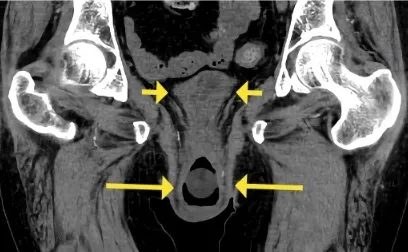

¡Atención al uso prolongado de Nitrofurantoína en ITU recurrente!

¡Atención al uso prolongado de Nitrofurantoína en ITU recurrente!

Siempre debemos prestar atención a los efectos secundarios de los medicamentos más comúnmente utilizados. ¡Echa un vistazo a este caso clínico!